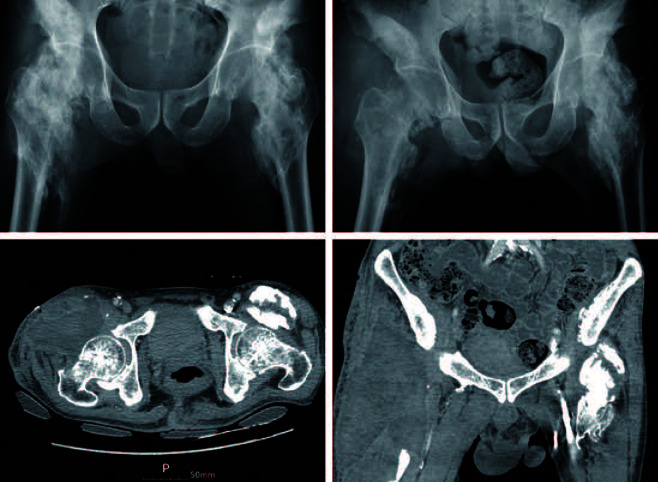

Purpose: Resection remains the most reliable treatment for established heterotopic ossification, despite questions regarding its effectiveness due to the potential for complications. This study evaluated the clinical outcomes and complications of neurogenic heterotopic ossification (NHO) resection in stroke patients' ankylosed hips.

Materials and methods: We retrospectively analyzed nine hip NHO resections performed on seven patients from 2010 to 2018. The pre- and postoperative range of motion of the operated hip were compared. Analysis of postoperative complications, including infection, recurrence, iatrogenic fracture, and neurovascular injury was performed.

Results: The mean operative time was 132.78±21.08 minutes, with a mean hemoglobin drop of 3.06±0.82 g/dL within the first postoperative week. The mean duration of postoperative follow-up was 52.08±28.72 months for all patients. Postoperative range of motion showed improvement from preoperative. Flexion and external rotation (mean, 58.89±30.60° and 16.67±18.03°, respectively) showed the greatest gain of motion of the operated hip joint. Postoperative infections resolved in two cases through surgical debridement, and one case required conversion to total hip arthroplasty due to instability. There were no recurrences, iatrogenic fractures, or neurovascular injuries.

Conclusion: Resection is a beneficial intervention for restoring the functional range of motion of the hip in order to improve the quality of life for patients with NHO and neurological disorders. We recommend performance of a minimal resection to achieve a targeted functional arc of motion in order to minimize the risk of postoperative complications.